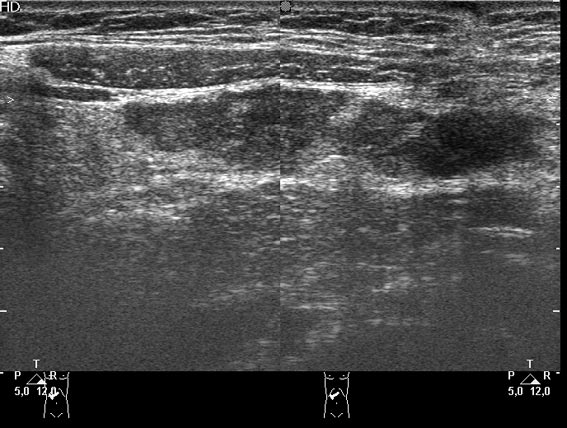

Девочка-подросток поступила в приемное отделение с жалобами на боли в эпигастральной области. На животе - рубец после срединной лапоротомии - полгода назад оперирована по поводу травмы и разрыва селезенки, со слов мамы - выполнена спленэктомия.

При УЗИ в эпигастральной области обнаружилось такое образование.

что-то в сальнике, но не инородное тело. может быть ошметок селезенки (аутотрансплантат)? васкуляризация есть?

Да, действительно, это аутотрансплантат ткани селезенки в большой сальник.

Если в типичном месте и не выполнялась аутотрансплантация, то это может быть гипертрофия т.н. дополнительной селезенки.